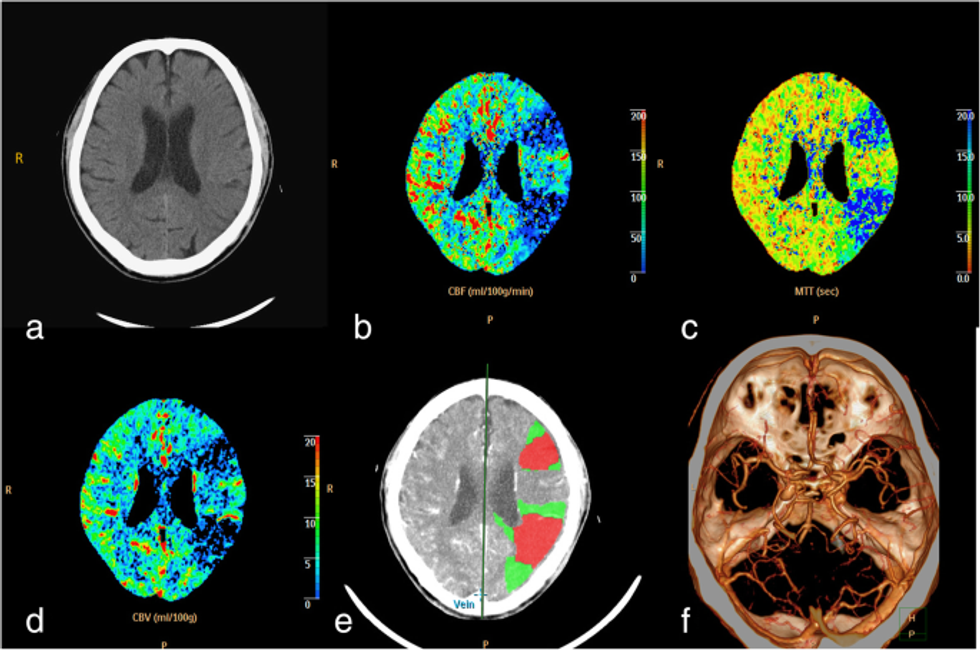

Për të diagnostikuar afazinë, duhet të kryhen disa teste si CT e kokës ose imazhe me rezonancë magnetike.